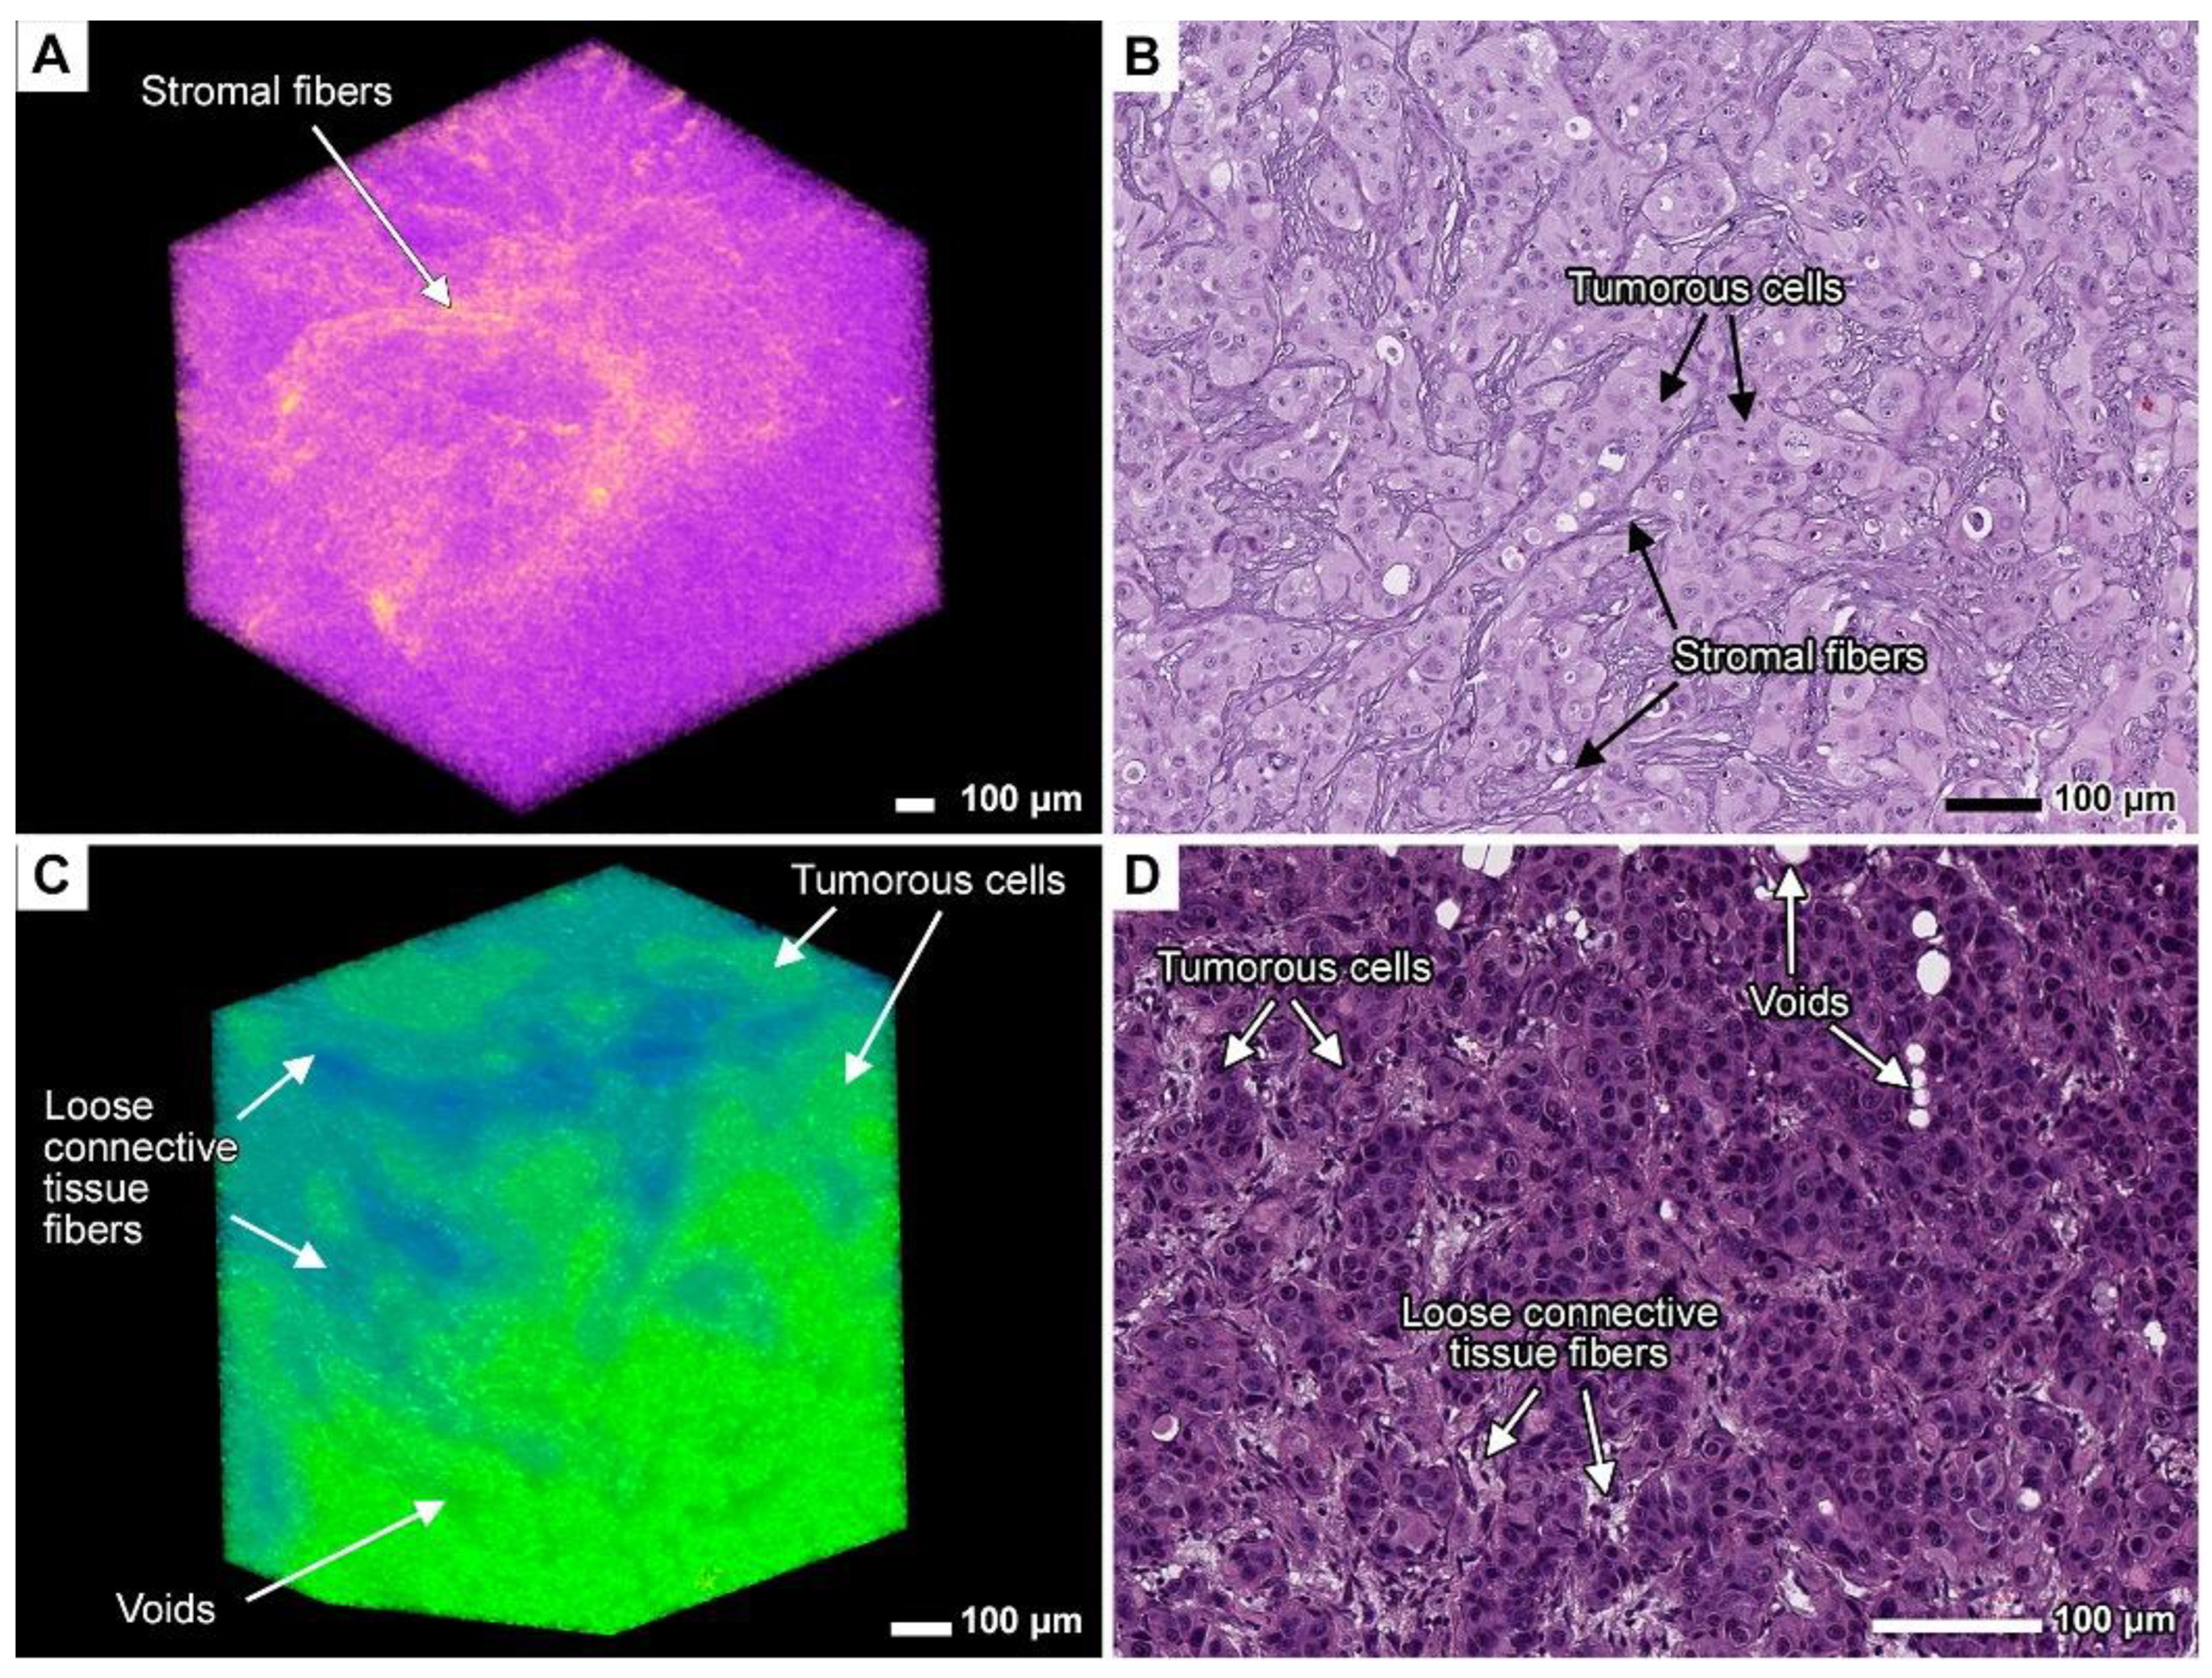

3.1. Method Validation

3.7. Stromal Connective Tissues Define Patterns of Invasion

3.8. Expanding the Concept of Tumor Clusters